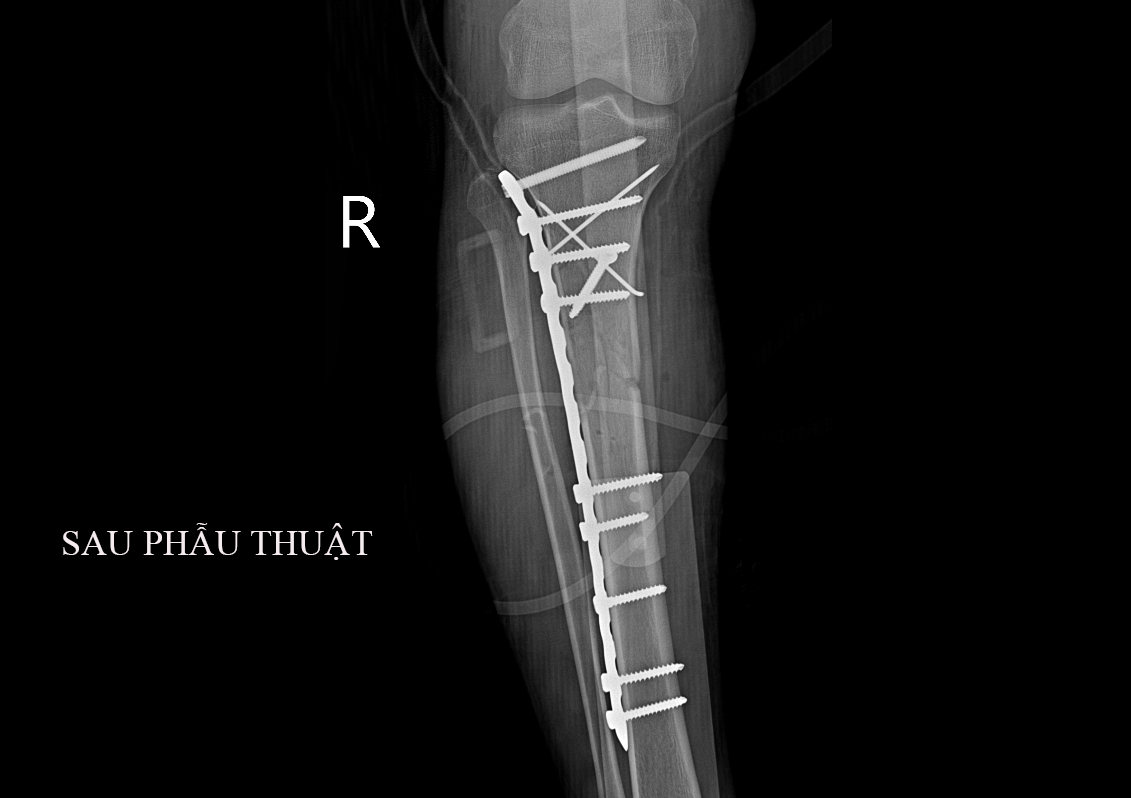

Ca mổ được bác sỹ Ma Công Thùy – Phó Trưởng khoa ngoại cùng ekip phẫu thuật, gây mê đã tiến hành phẫu thuật kết hợp xương chày bằng phương pháp nẹp vít cho bệnh nhân. Sau hơn 2 giờ kíp phẫu thuật đã thực hiện thành công ca phẫu thuật. Kết quả X - quang sau phẫu thuật: Hình ảnh xương thẳng trục, mảnh xương vỡ đúng vị trí. Đây là một ca phẫu thuật khó, vì xương gãy thành nhiều mảnh nhỏ, phức tạp. Thời gian phẫu thuật kéo dài. Hiện tại, bệnh nhân tiếp tục được chăm sóc và điều trị tại khoa. Dự kiến sẽ được xuất viện trong vài ngày tới.

Hình ảnh XQ sau phẫu thuật của bệnh nhân